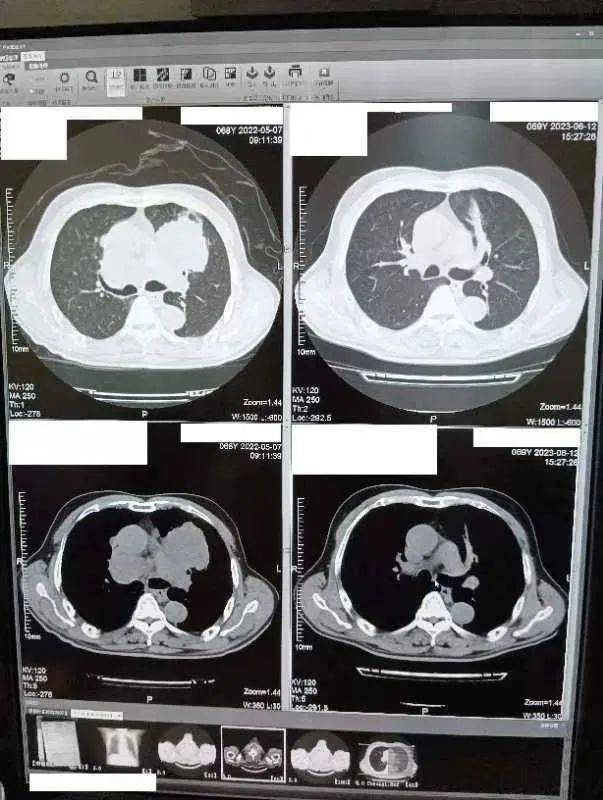

最早确诊和最后一次CT检查对比图:

图片来源:患者提供(点击查看原图)